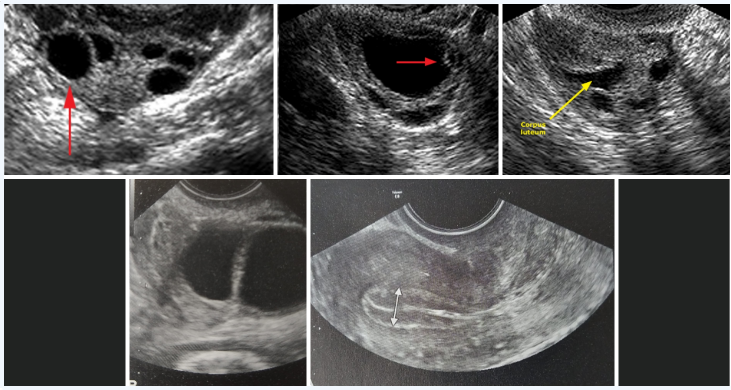

• Ultrasound monitoring

Medication Combination: Typically, a combination of oral fertility medication with or without injectable fertility hormones, like follicle-stimulating hormone (FSH), human menopausal gonadotropin (HMG) is used. This combination encourages the ovaries to produce one or more mature follicles.

Mature Follicles: Each mature follicle contains one egg capable of being fertilized. In cases where women do not have regular menstrual cycles and do not ovulate normally, the aim is to produce one mature follicle to restore normal ovulatory function.

For women with regular menstrual cycles and ovulation, controlled ovarian hyperstimulation is employed to "superovulate" them. Stimulation more than one follicle is referred to as “Superovulation.” This process increases the likelihood of pregnancy by producing more than one mature follicle each month.